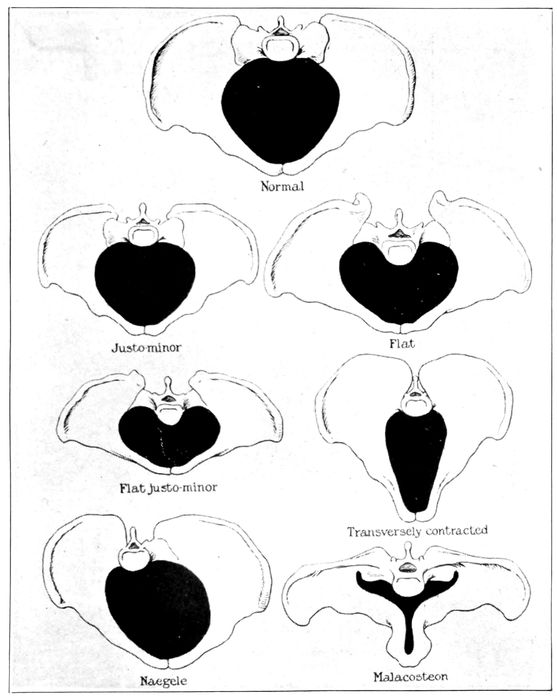

| 93. |

215 |